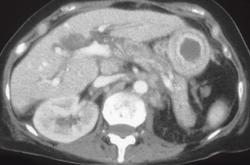

Diagnosis

Linitis Plastica